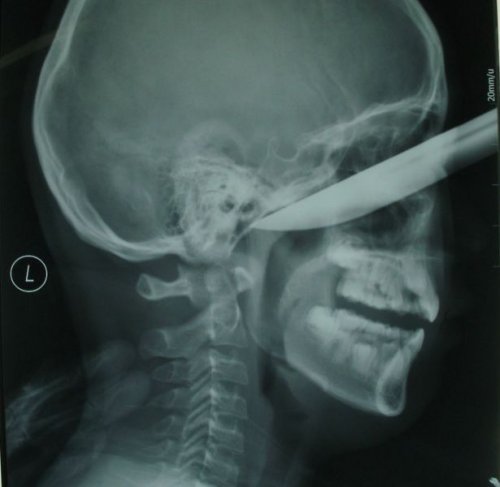

16-летний подросток обманул смерть, когда ему в голову вонзили 12-сантиметровый нож. Подростка отвезли в больницу с кухонным ножом, торчащим из его лба.

Китайский подросток поскользнулся и вонзил себе в лицо 7-сантиметровый нож, которым чистил яблоко. Отец Рена Ханжи (Ren Hanzhi) вспоминает: «Он шёл к дивану и на ходу чистил яблоко. Вдруг он поскользнулся и в его лицо вонзился острый нож. Я не решился вытаскивать нож, так как мой сын громко кричал». Главный хирург Пень Ливей (Peng Liwei), который проводил операцию по извлечению ножа, прокомментировал: «Это шокирующий случай. Нож, длина которого превышает 20 сантиметров, на 7 сантиметров вошёл в лицо мальчика». Операция прошла успешно, и пациент полностью восстановился примерно за месяц.